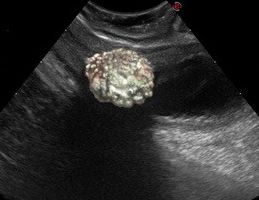

皮膚リーシュマニア症は皮膚に潰瘍ができ、通常は2~3ヶ月で自然治癒しますが、醜い瘢痕(はんこん)が残ることもあります。これらのびらんは、馬の鼻口部、耳介、陰嚢、頸部、下肢および眼窩周囲に発生します。

●皮膚のびらん